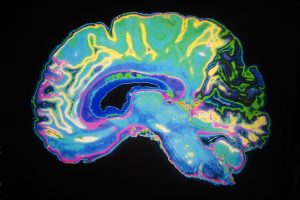

Artificially,Colored,Mri,Scan,Of,Human,Brain